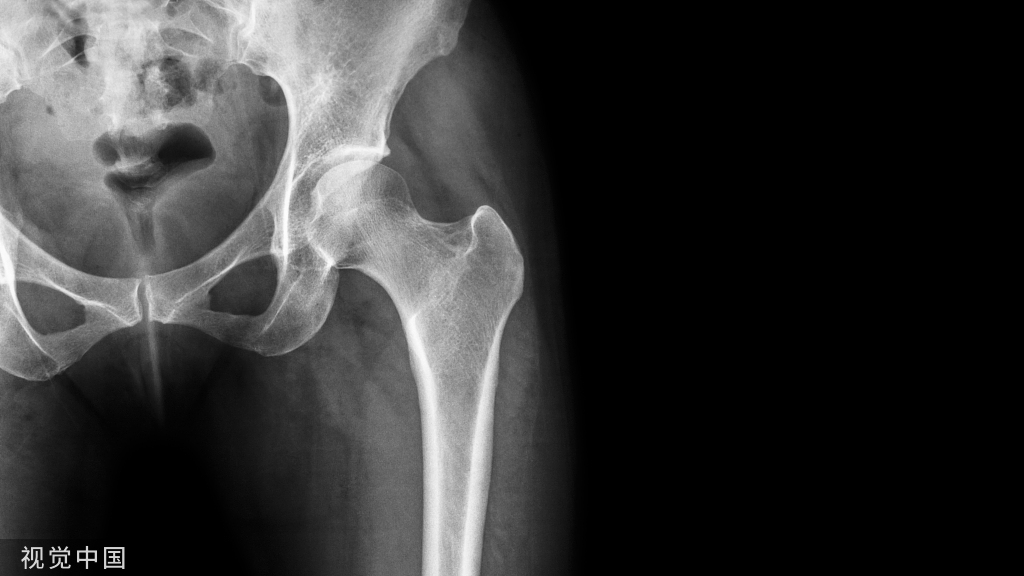

术后随访时的侧位腰椎X线片显示的骨折及内固定情况,患者最终预后良好。